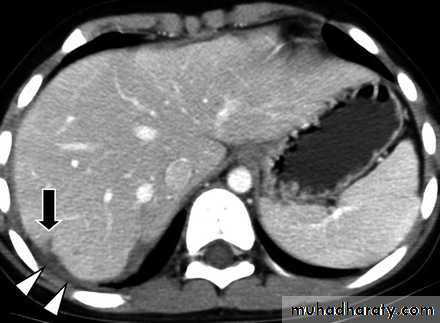

CT Scans

Accurate in localizing the site of liver injury and any associated injuries

Used to monitor healing

CT criteria for staging liver trauma uses AAST liver injury scaleGrades 1-6

Classification(AASTI-Subcapsular hematoma<1cm, superficial laceration<1cm deep.

Subcapsular hematoma